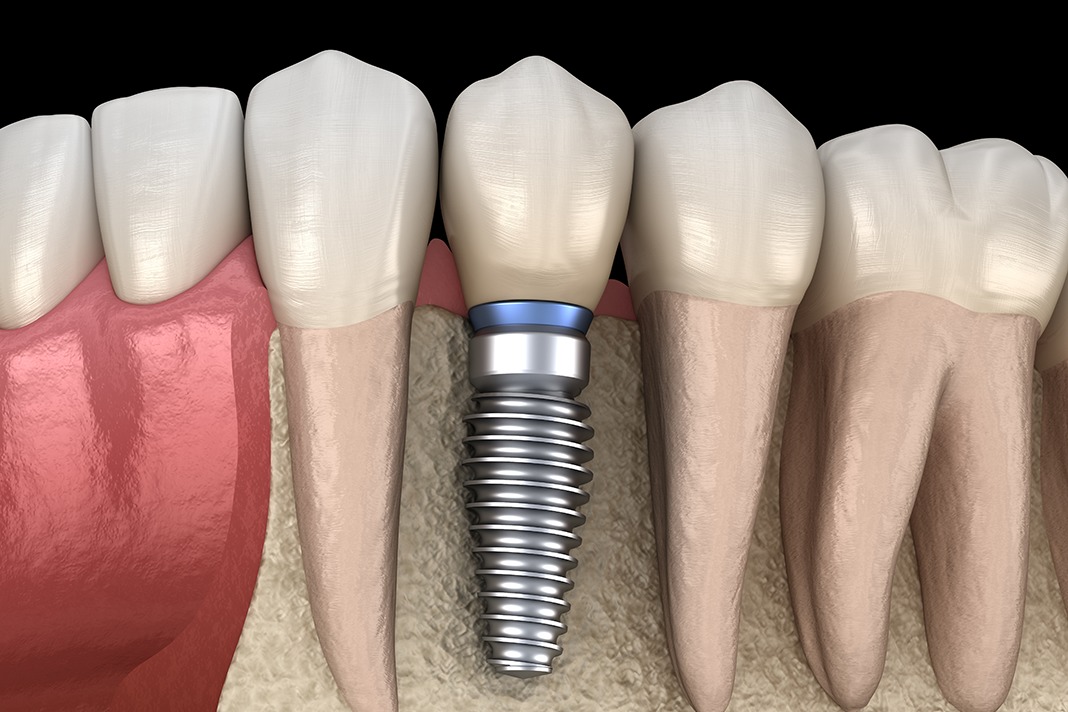

Dental Implant Problem . There are methods to fix these reasons for failure, but it can be a long and invasive process. Here, learn six things that impact the success of dental implants. What can i do about them myself, and what requires a professional? If your dental implant fails, you and your dentist can decide if you should replace the implant or try another option. Dental implant surgery is a procedure that replaces tooth roots with metal, screwlike posts and replaces damaged or missing teeth with artificial teeth that look and. Dental implants are permanent false teeth. Dental implants have a high success rate, but some people experience dental implant failure. Medically reviewed by zilpah sheikh, md on february 01, 2024. Dental implants are a groundbreaking modern solution to a problem that's historically worried humans: Reasons for dental implant failure include teeth grinding, an allergic reaction to the materials used, poorly made dental impressions, infection, nerve damage, movement of the implant, issues with underlying jawbones, and various medication conditions. What problems are common with dental implants? A dentist may recommend dental implants for you if you’re missing teeth or need.

Dental implants have a high success rate, but some people experience dental implant failure. There are methods to fix these reasons for failure, but it can be a long and invasive process. Dental implants are permanent false teeth. A dentist may recommend dental implants for you if you’re missing teeth or need. What can i do about them myself, and what requires a professional? If your dental implant fails, you and your dentist can decide if you should replace the implant or try another option. Medically reviewed by zilpah sheikh, md on february 01, 2024. Dental implants are a groundbreaking modern solution to a problem that's historically worried humans: Reasons for dental implant failure include teeth grinding, an allergic reaction to the materials used, poorly made dental impressions, infection, nerve damage, movement of the implant, issues with underlying jawbones, and various medication conditions. What problems are common with dental implants?